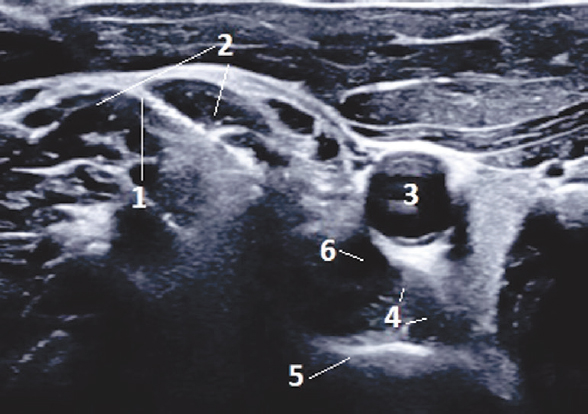

При сохраняющейся неэффективности консервативной терапии НБС в течение 4–6 нед после обязательного контрольного инструментального обследования, включающего в себя ЭНМГ и УЗИ, следующим этапом оказания помощи является оперативное нейрохирургическое вмешательство на невральных структурах, являющихся источниками невропатической боли: невролиз нервов и сплетений с целью устранения периневрального рубцово-спаечного процесса, иссечение сформировавшихся боковых или внутриствольных невром, удаление ранее не верифицированных интраневрально или параневрально расположенных инородных тел (ранящих снарядов), костных отломков (рис. 6).

Рис. 6. Компрессия правого седалищного нерва костным отломком бедренной кости после огнестрельного многооскольчатого перелома: 1 — бедренная кость; 2 — костный отломок; 3 — малоберцовая порция седалищного нерва (гипоэхогенная структура, нервные фасцикулы не визуализируются); 4 — большеберцовая порция седалищного нерва (структура фасцикул сохранена); 5 — зона выраженного периневрального отека